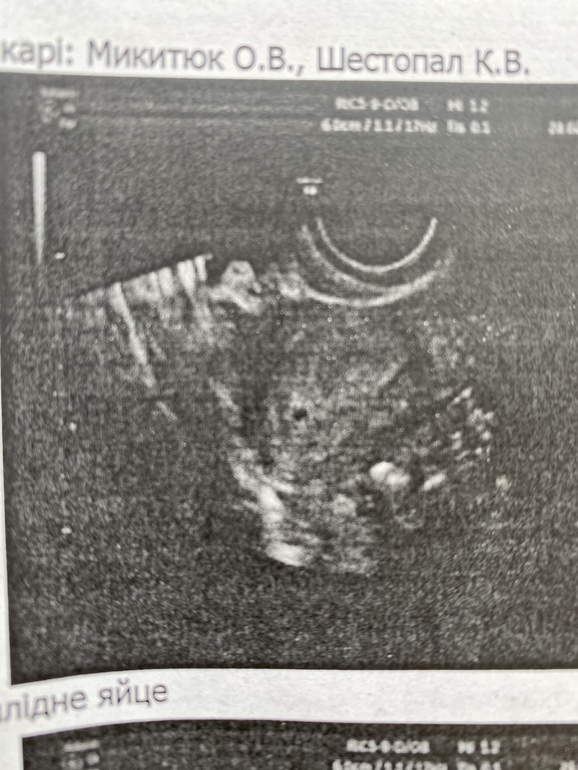

Узи на 14дпо. обновлено, узи на 17дпо(фото)

Беременность- 1 триместр ( только до 10 недель)Вчера (14дпо) была на узи, контролируют жидкость в позадиматочном пространстве.

Нашли плодное яйцо 1,4мм

Сказали, пока еще рано говорить, что это все точно, но включение есть,

эндометрий 18,2мм,

жт 19*17,8

17 дпо: